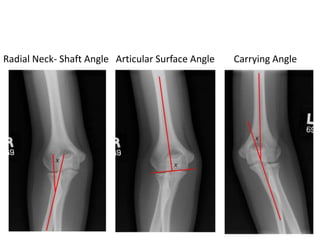

Measurements on AP radiograph

1. Radial Neck- Shaft Angle

2. Articular Surface Angle

3. Carrying Angle

Radial Neck- Shaft Angle Articular Surface Angle Carrying Angle